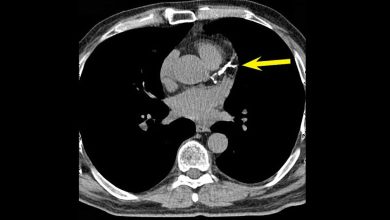

"النمر": تكلّس الشرايين قد يرتفع 25٪ سنويًّا دون خطورة.. واستخدام الأسبرين مشروط بـ3 عوامل